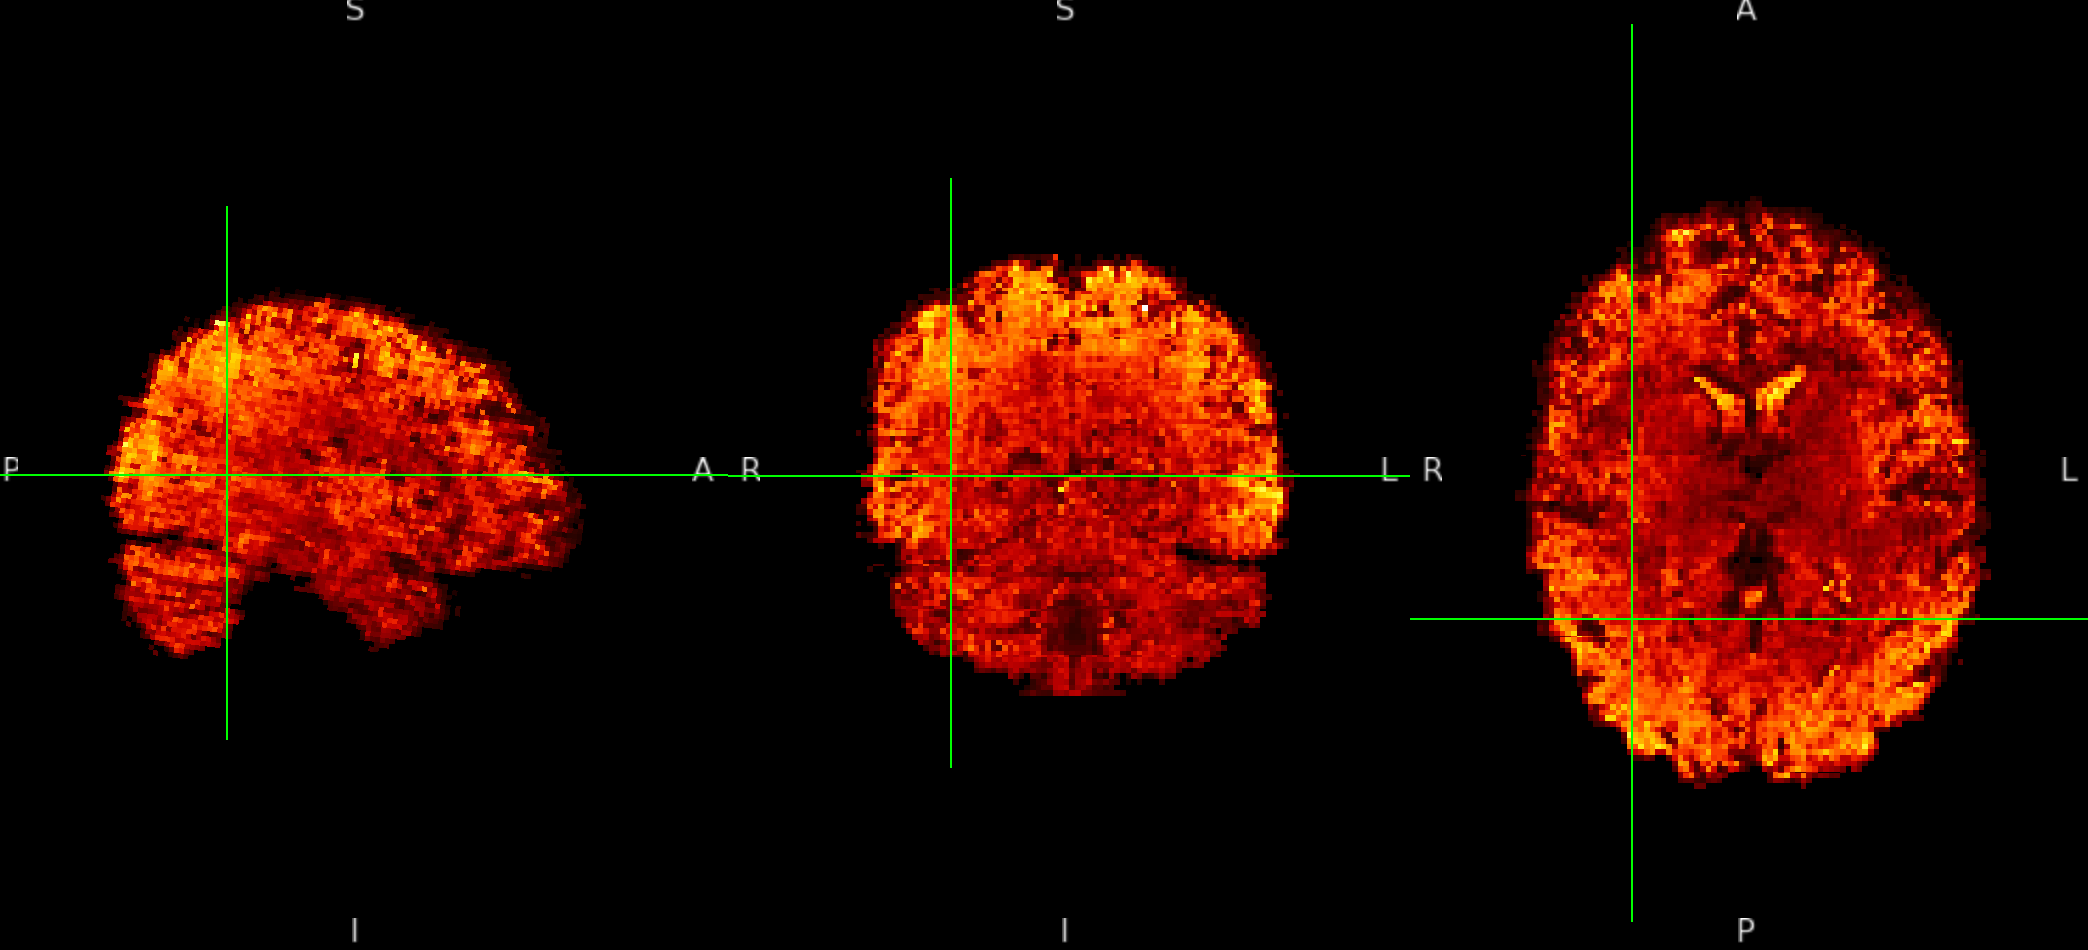

ME sequence in MNI152NLin6Asym-res1

The checkerboard pattern is more evident in the ME sequence where it is also visible outside the brain, but it is present in both, ME and SE inside the brain.